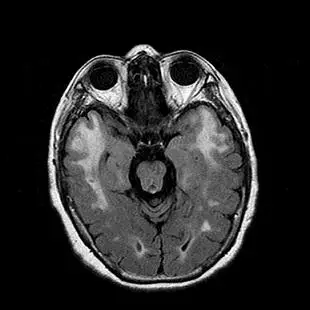

54歲女性主訴最近三年來記憶力減退,她在 49歲時曾發生右側肢體無力,後來完全恢復。她的簡易智能測驗(Mini-Mental State Examination )得分 22分(滿分 30分),她的父親、叔叔和哥哥都有中風和失智的病史。她的腦部磁振造影掃描結果如下圖,她最有可能是那一個基因變異?

由所示腦部MRI影像(疑為FLAIR或T2序列),可見:

- 額顳葉深部白質呈對稱性高訊號(白質病變),尤其是顳極(anterior temporal pole)區域可見明顯髓鞘流失的白質高訊號。

- 影像左、右兩側外囊(external capsule)區域亦可見白質高訊號斑點。

- 未見皮質灰質明顯萎縮,亦未見大範圍梗塞或腫塊病灶增強。 這種前顳葉及外囊優先受累的白質高訊號分佈,與CADASIL極為吻合 (radiologica.org)。

CADASIL即由NOTCH3基因突變所致,常表現為30–50歲間反覆小中風(lacunar infarcts)、偏頭痛和進展性認知功能減退;MRI特徵為顳極及外囊白質T2/FLAIR高訊號。家族呈顯性遺傳,本題中